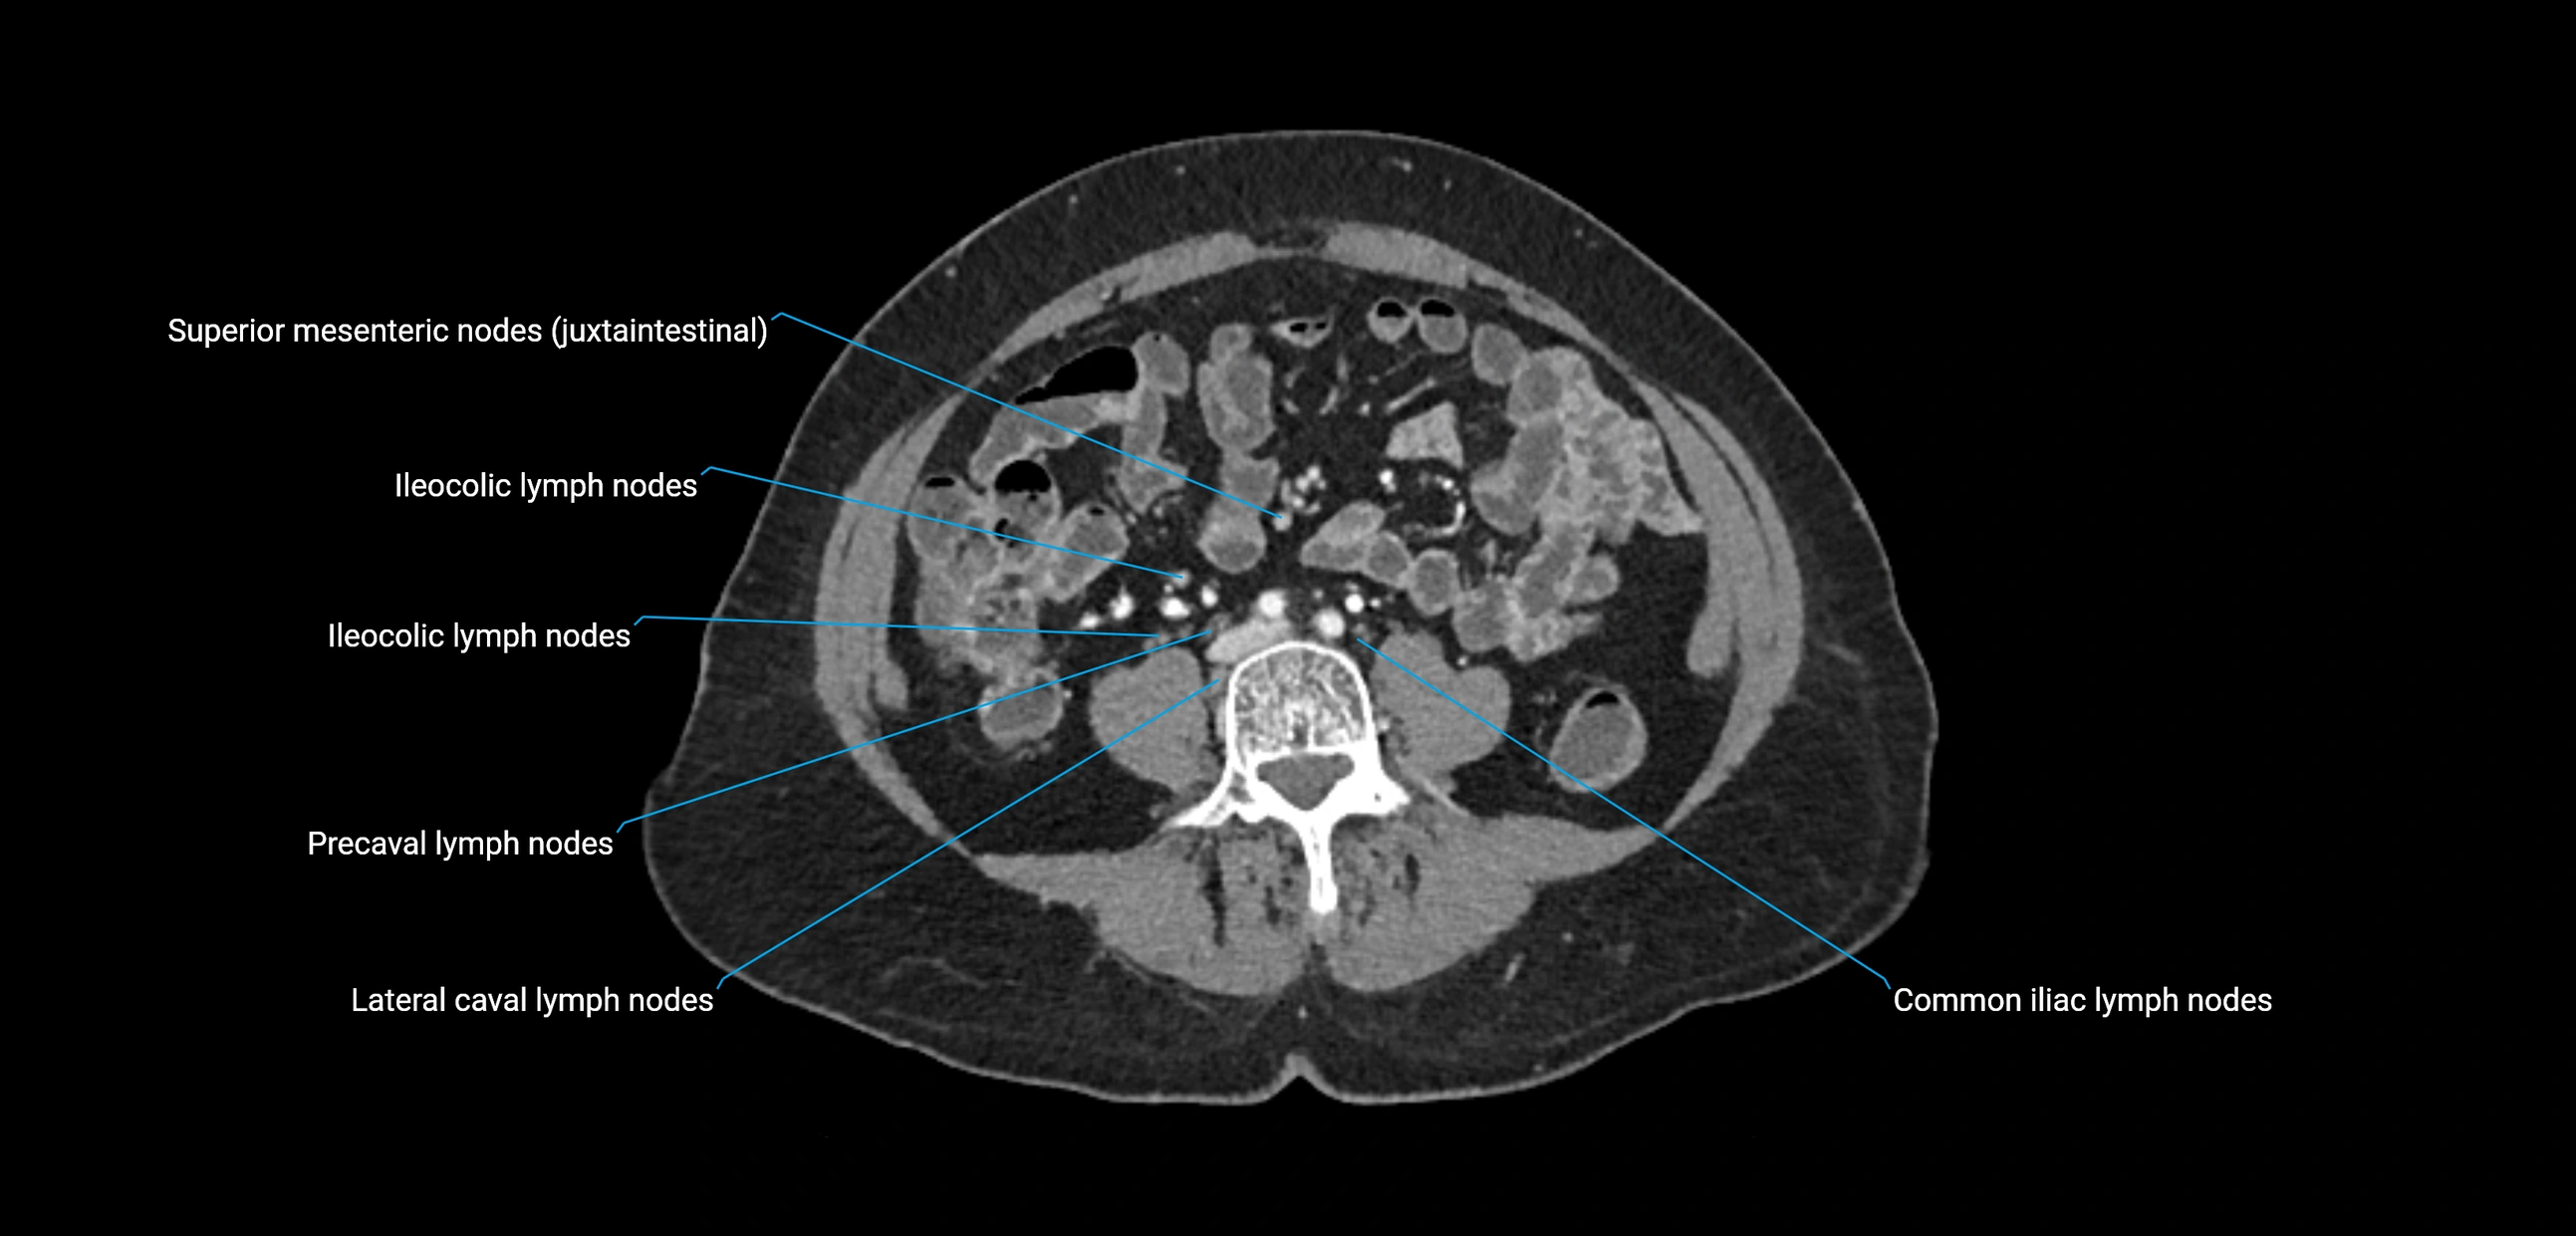

The lateral aortic lymph nodes (also called para-aortic lymph nodes) are a major group of retroperitoneal lymph nodes located along the abdominal aorta and its branches. They lie between the diaphragmatic crura superiorly and the bifurcation of the aorta at L4 inferiorly.

These nodes receive lymph from a wide range of abdominal and pelvic structures. Specifically, they drain lymph from the kidneys, suprarenal glands, gonads (testes/ovaries), uterus, uterine tubes, and pelvic organs, before converging into the lumbar lymphatic trunks, which terminate in the cisterna chyli → thoracic duct.

Clinically, the lateral aortic lymph nodes are critically important in oncology, being involved in the spread of testicular cancer, ovarian cancer, endometrial cancer, cervical cancer, renal malignancies, and retroperitoneal lymphomas. They are also key targets in retroperitoneal lymph node dissection (RPLND) for testicular tumors.

CT Appearance

CT Post-Contrast:

• Normal nodes enhance homogeneously

• Malignant nodes may show heterogeneous enhancement, central necrosis, or conglomerate formation

• Size >1 cm short axis is suspicious, though morphology and distribution are equally important

CT Venography (CTV):

• Demonstrates nodal encasement or compression of adjacent vessels (aorta, IVC, renal veins)

• Useful in staging testicular and ovarian malignancies

• Provides 3D reconstructions for retroperitoneal lymph node dissection planning